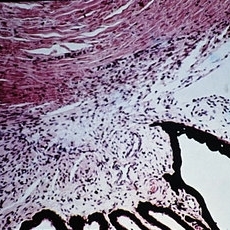

Slide 12-4

Feb 27 2019 by Lancaster Course in Ophthalmology

Congenital glaucoma. The ruptured end of a Descemet's membrane has healed over so that the scroll-like extension of the membrane hanging into the anterior chamber is covered completely by endothelium (H&E xlOl).

Condition/keywords: congenital glaucoma , descemet's membrane